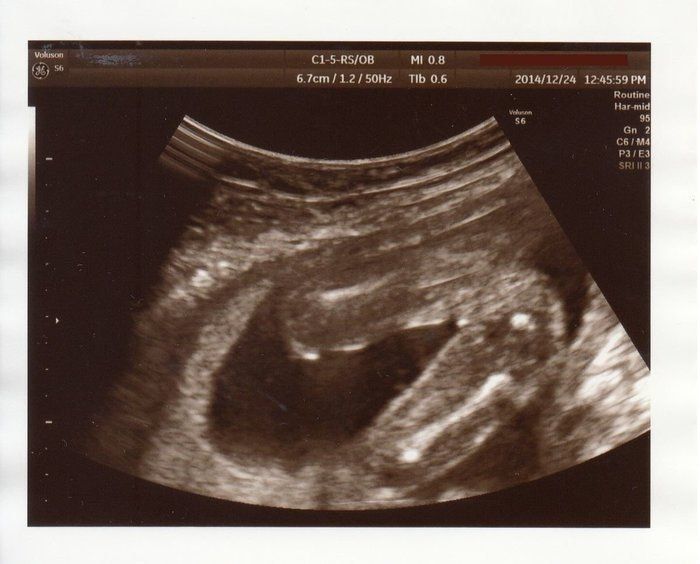

はやしなおさんの妊娠19週目のエコー写真 顔のパーツもエコーでわかるように

私が通う産婦人科では希望しない限りエコーは決められたときにしかなく、この日が久しぶりのご対面となりました。もうすっかり手足や顔のパーツが確認できるまでに成長し、赤ちゃんらしいシルエットになってきました。このころ長女の幼稚園通いが始まり、妊娠のために上の娘を積極的に外に遊びに連れて行ってあげられないジレンマは少し解消されました。幼稚園後、娘と遊んで過ごす時間を意識して、夕方から就寝の時間までに、たくさんのパワーを残しておくことを考えていました。